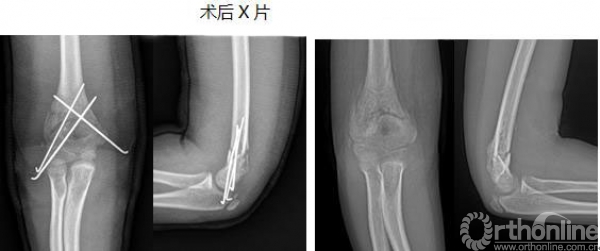

3.肱骨髁上骨折“零”切开。

华某某,12岁,男,完全移位的右肱骨髁上骨折,行肱骨髁上骨折“零”切开手术,术后恢复良好,不留疤,在门诊取内固定可立即离院。